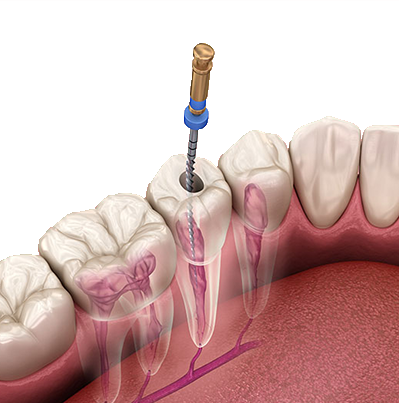

Painless RCT

Advanced root canal treatment designed to remove infection, relieve pain, and preserve your natural tooth comfortably and safely.